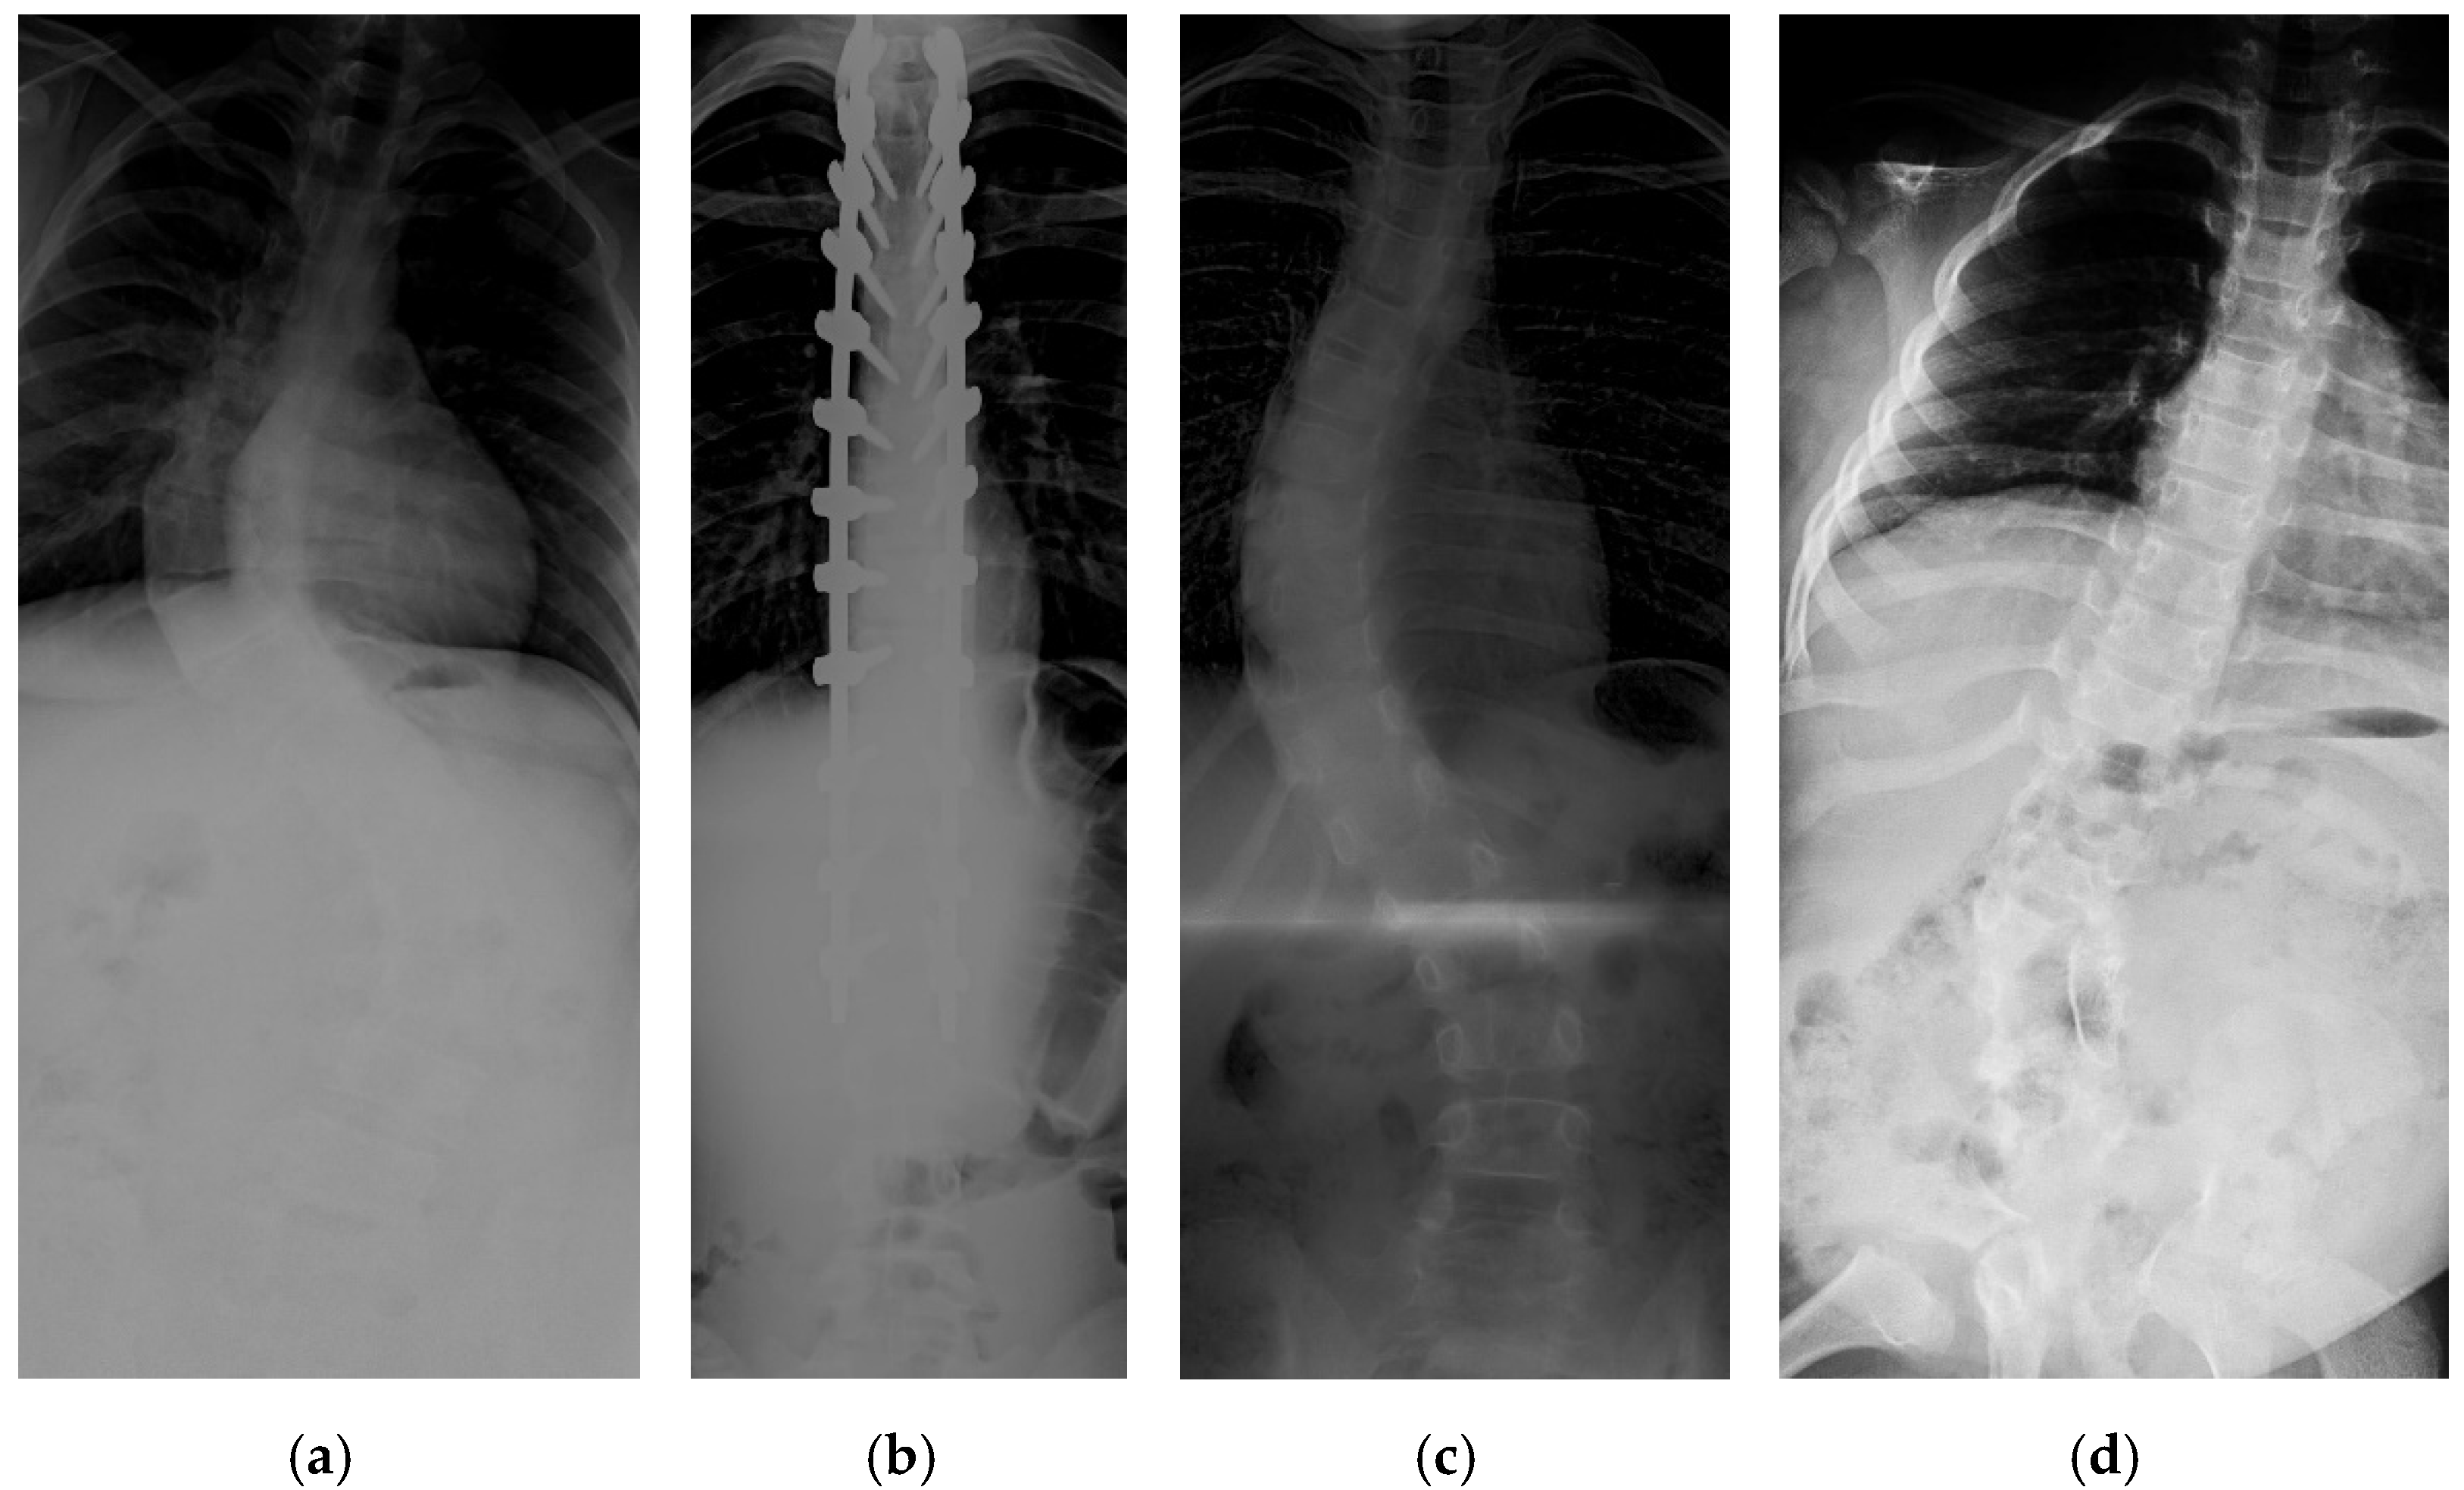

Figure A1.

The red font inside the X-ray image is a CNN CA measurement. Observer 1 and 2 evaluation is presented on the bottom left and right, respectively.